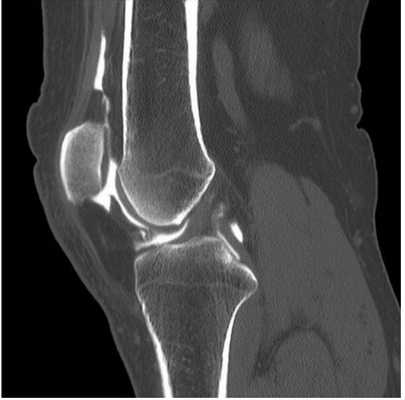

Компьютерная томограмма коленного сустава (сагиттальная проекция)

Стандартные проекции, применяемые при рентгенографии коленного сустава - прямая (передне-задняя) и боковая (рис.1). По мере необходимости их дополняют правой или левой косой, а также аксиальной проекциями. Основным правилом при рентгенологическом исследовании коленного сустава является полипозиционность.

- в боковой проекции:

- возможность просмотра надколенно-бедренного сустава и бугристости большеберцовой кости.

Рентгенологическое исследование коленного сустава в прямой проекции обязательно дополняется боковым снимком. При боковой рентгенографии центральный луч проходит по суставной щели с уклоном на 10° в каудо-краниальном направлении. При этом края мыщелков бедренной кости накладываются друг на друга и их суставные поверхности смещаются в своей задней нижней части. Это позволяет хорошо различать их контуры и оценить состояние бедренно-надколенникового сочленения.

Боковой снимок коленного сустава производится либо в положении пациента лёжа на боку, в условиях полной расслабленности сустава, либо стоя, без нагрузки на исследуемый сустав. Лёгкое сгибание колена, равное 30° или 15°, позволяет определить состояние бедренно-надколенникового сочленения. Сгибание предназначено для визуализации надколенника в момент его внедрения в межмыщелковое пространство (трохлею).

- Указанная проекция позволяет:

- выявить транзиторную нестабильность, которая выражается в задержке вхождения надколенника в трохлею, и которая может исчезнуть при 30° сгибания или не выявляться на аксиальном снимке, когда минимальное сгибание равно 30°;

- оценить высоту надколенника и состояние его суставной поверхности.